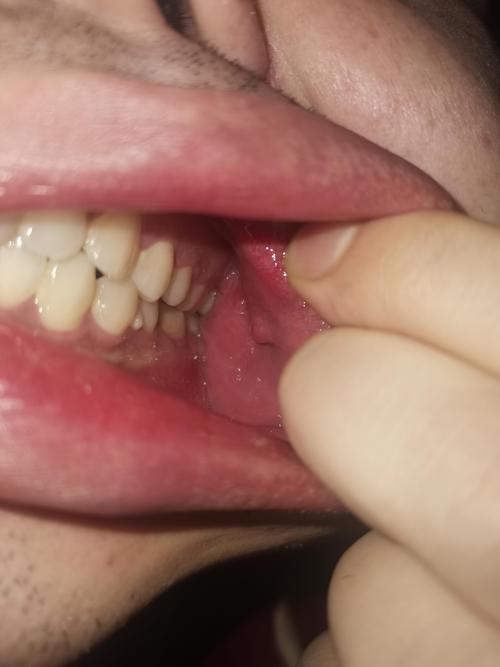

口腔息肉的本质是口腔黏膜的良性增生性赘生物,您可以把它想象成皮肤上长出来的“肉疙瘩”,它的形成是由于局部的慢性刺激、炎症或组织修复异常,导致黏膜下的细胞异常增生,堆积在一起形成了新的、多余的组织。

- 外观:通常是一个表面光滑、质地较硬、呈粉红色或白色的圆形或椭圆形小肉疙瘩,大小不一,一般没有疼痛感。

- 外观:生长速度非常快,颜色鲜红或暗红,表面光滑,质地柔软,容易出血。